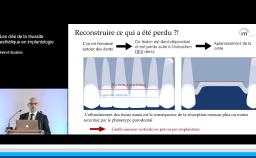

La présentation s’attache à détailler en quoi l’implantation en zone esthétique constitue un challenge lorsqu’il s’agit de réhabiliter la fonction sans oublier de rétablir l’esthétique. A travers quelques cas cliniques, le Dr Eycken s’appuie sur la classification SAC de l’ITI pour évaluer la complexité du cas et y apporter la solution thérapeutique adaptée. Il revient également sur l’importance du positionnement de l’implant dans les 3 sens de l’espace et sur la qualité des tissus mous environnants.

- de positionner un implant correctement dans les 3 plans de l’espace